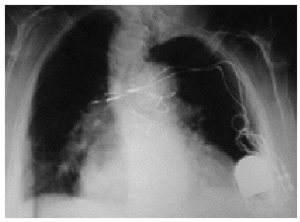

El primer caso se presentó en una mujer de 72 años, con deterioro intelectual moderado por demencia senil e intervenida de bypass aortocoronario años atrás. La paciente ingresó por presentar enfermedad del seno sintomática y se implantó un marcapasos DDDR. Las radiografías y los seguimientos posteriores al implante fueron normales. Dos meses tras el alta, la enferma acudió a consulta por no tar estimulación pectoral derecha. En la radiografía (fig. 1) se observaba un "trenzado de ambos cables" en un eje vertical, con desplazamiento de los electrodos hasta la vecindad del pectoral derecho. La paciente reconocía haber manipulado el generador. Se recolocaron los cables (fig. 2) y el generador se suturó a la fascia del pectoral.

Figura 1. Radiografía posteroanterior de tórax en la que se observan el desplazamiento inferior del generador y el "trenzado" de los cables en el eje vertical. Los electrodos han perdido contacto con el endocardio y están en la zona subpectoral derecha.